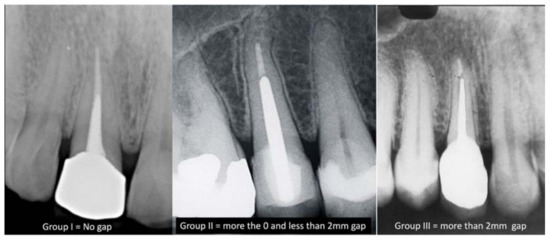

توضیحاتساخت چین Made in Chinaبسته بندی : 120 عددیدارای شماره های : 15-20-25-30-35-40-45-50-55-60-70-80کیفیت عالی و کاملا طبیعیانعطاف مناسبتیپر استانداردمطالعه آسان در فتوگرافی